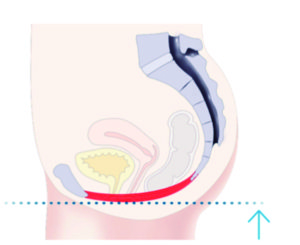

TRƯỚC

Các cơ sàn chậu không đủ khả năng hỗ trợ các cơ quan vùng chậu và ảnh hưởng đến khả năng kiểm soát bàng quang.

ĐIỀU TRỊ

Bàn tập cơ sàn chậu kích thích hiệu quả các cơ sàn chậu với hàng ngàn con co thắt cơ mỗi lần điều trị.

SAU ĐIỀU TRỊ

Kích thích làm khỏe cơ sàn chậu, giúp lấy lại khả năng kiểm soát các cơ sàn chậu và bàng quang.